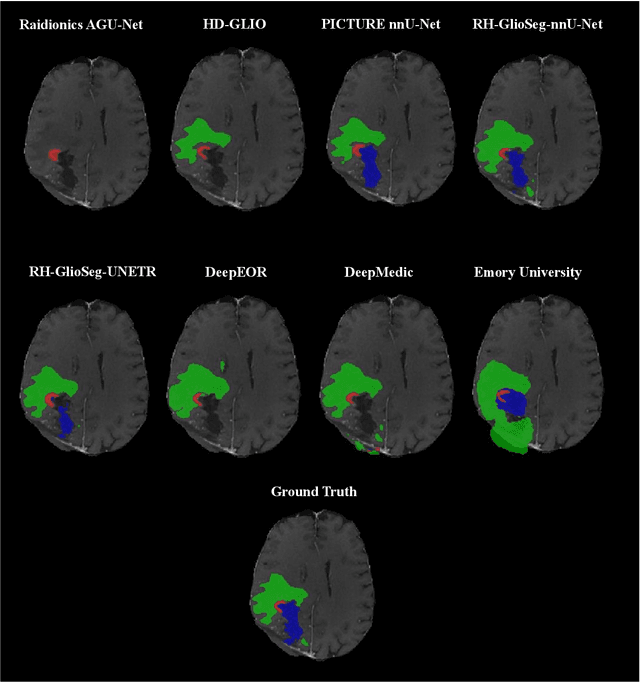

Abstract:Accurately assessing tumor removal is paramount in the management of glioblastoma. We developed a pipeline using MRI scans and neural networks to segment tumor subregions and the surgical cavity in postoperative images. Our model excels in accurately classifying the extent of resection, offering a valuable tool for clinicians in assessing treatment effectiveness.